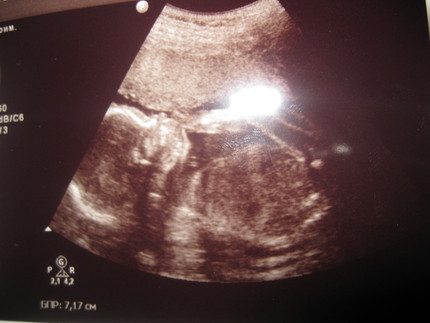

23-я неделя беременности..+ ФОТО — 50 ответов

23-я неделя беременности..уже 23-я ..Вроде недавно экватор был)))

10. 9 января на УЗИ))

Плод в 23 недели беременности хоть и наращивает жир весьма интенсивно, но вид ещё, как говорится, не очень. Если ваш срок — 23 неделя беременности, на фото ваш малыш вышел бы сморщенным, красным и с обвисшей кожей.

Вес вашего малыша 23 неделя беременности увеличивает приблизительно до 500 граммов, рост — до 30 сантиметров.